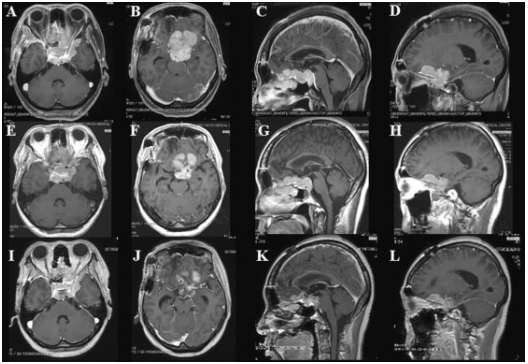

在观察过程中,与之前报道的最初的HGMs病例一样,所有的SBM患者都表现出体积减少损伤。不过所有肿瘤均呈逐渐缩小的趋势,部分患者BNCT后出现短暂性增大,通常在放疗后一个月内,再逐渐减小;这种模式被称为假性进展(?图1)。?图2表示肿瘤缩小的一个实例。患者为49岁女性,前颅底出现非典型脑膜瘤。在BNCT术后3个月,患者的容积减少了30%。